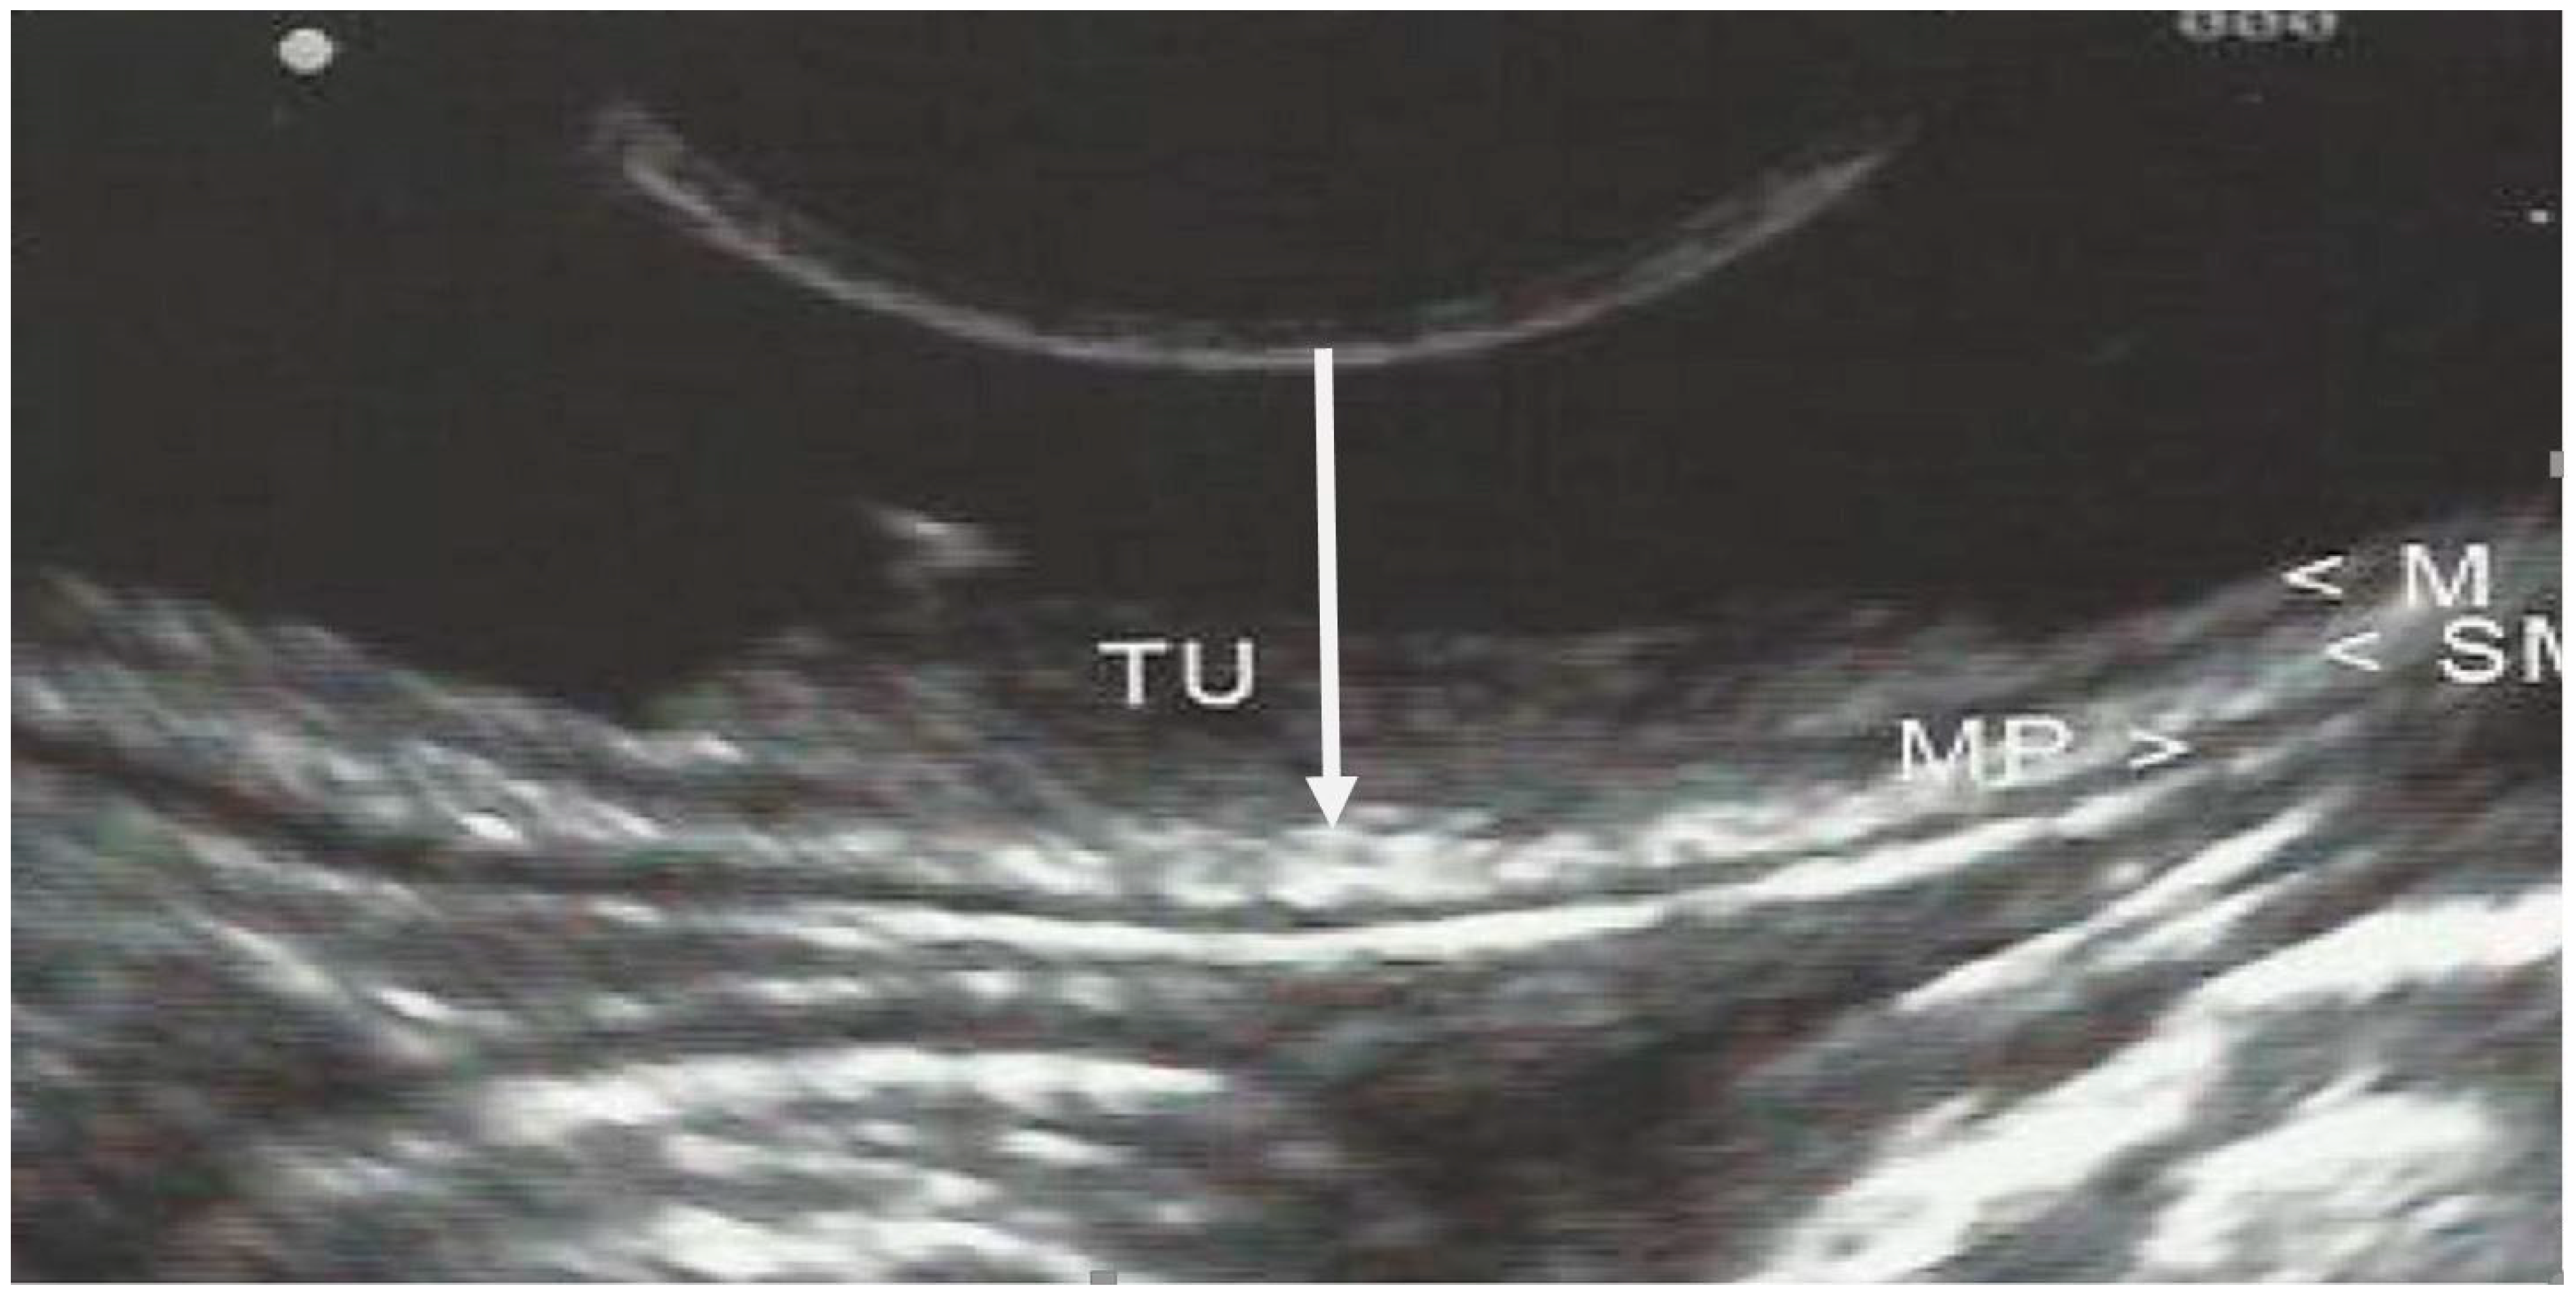

3. EUS Technique